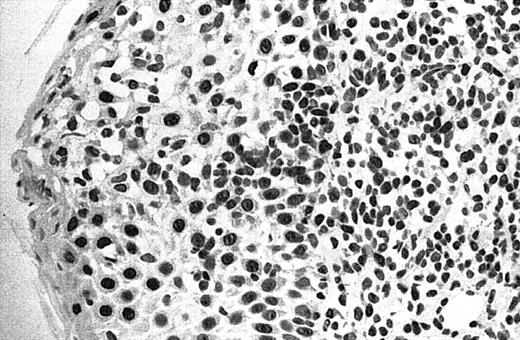

Of 69 PCLs analyzed by IHC, 44 cases showed nuclear JUNB expression in a proportion of tumor cells (64%) (Table 2). This included 21 (91%) of 23 SS, 6 (75%) of 8 C-ALCL, 5 (50%) of 10 MF, 9 (43%) of 21 PCBCL, 2 (50%) of 4 NK cell lymphoma, and 1 (50%) of 2 systemic FL (Table 2). Seven cases (10%) revealed expression of JUNB by all tumor cells (+++) (overexpression), including 5 C-ALCL (63%) and 2 SS cases (9%) (Table 2; Figures2-3). Epidermal basal and suprabasal keratinocytes also expressed JUNB, which represented a useful internal control to indicate the efficiency of immunohistochemistry (Figure 2). All the positively stained PCBCL cases showed only occasional cells expressing JUNB (+) (Table 2), and in this case it is difficult to conclusively establish whether expression is restricted to tumor cells or activated B cells on morphology.

Illustration of IHC staining of JUNB in an SS patient (case 8).

This photograph (original magnification × 40) revealed strong nuclear expression of JUNB by large epidermotropic tumor cells with absent expression in small dermal mononuclear cells. Epidermal basal keratinocytes also expressed JUNB, representing a useful internal control.